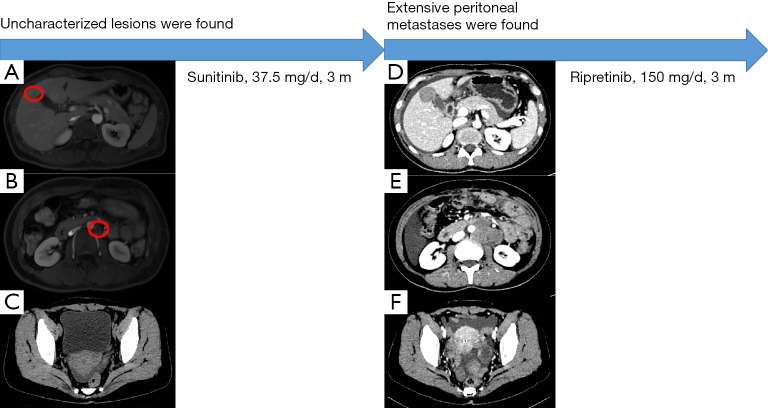

鑒于腫瘤對伊馬替尼有耐藥性,患者在手術后口服舒尼替尼(37.5 毫克/天)。 患者狀態(tài)良好,未發(fā)生藥物不良反應。 2021 年 1 月的腹部 CT 掃描未見明顯異常。 2021年5月腹部磁共振復查示肝右前葉異常信號,較2021年1月結果新,考慮血管瘤可能性大(見圖2A)。 此外,在腹主動脈左側觀察到淋巴結腫大(見圖 2B),還有少量盆腔積液(見圖 2C)。

案例第 2 階段的圖形摘要。 (A) 無法識別的肝臟微觀病變(由紅色圓圈顯示)。 (B) 腹主動脈旁的小淋巴結(紅色圓圈所示)。 (C) 少量盆腔積液。 (D) 肝轉移。 (E) 主動脈旁轉移。 (F) 盆腔腹水和轉移性結節(jié)。

患者2021年8月的腹部CT顯示腹部和骨盆多處軟組織結節(jié)和腫塊,與2021年5月的結果相比是新的,考慮轉移。 腫瘤基因解碼醫(yī)師還注意到肝臟右前葉的低密度病灶比以前更大,并考慮轉移(見圖2D)。 此外,在腹主動脈周圍觀察到多個腫大的淋巴結,并考慮轉移(見圖2E),并且還觀察到腹部盆腔積液(見圖2F)。 鑒于患者腫瘤的基因突變類型,患者從三線 TKI 瑞戈非尼中獲益的可能性很小,因此患者接受了口服利培替尼(150 mg/天)治療。 2021年10月,患者繼續(xù)服藥,狀態(tài)良好但有輕微腹脹。 她將如期接受審查。